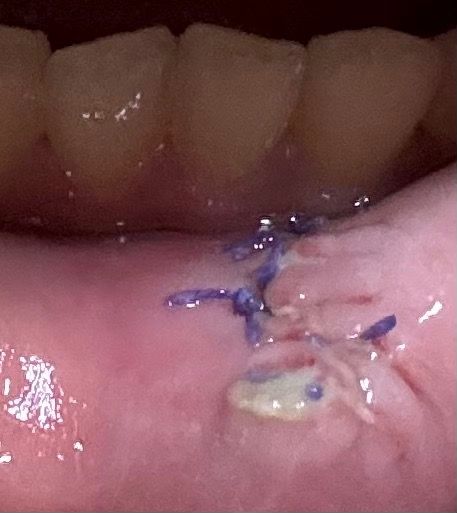

육아종 제거 수술을 화요일에 진행하였는데 수술 후 가장 크게 벌어져있던? 부위에 흰색 이물질같은 것이 생겼습니다

순서대로 수술 다음날 수요일, 금요일, 토요일입니다.

• 3번 째 사진

사진상으로 보면 잇몸이 아물면서 생기는 자연스러운 현상이니 너무 걱정하지 않으셔도 될것같습니다.

잇몸 흡수를 받게 되면 해당 부의 가피등이 형성될 수 있습니다. 이런 카피들은 흰색으로 보이게 되는데 크게 문제가 되지 않습니다.